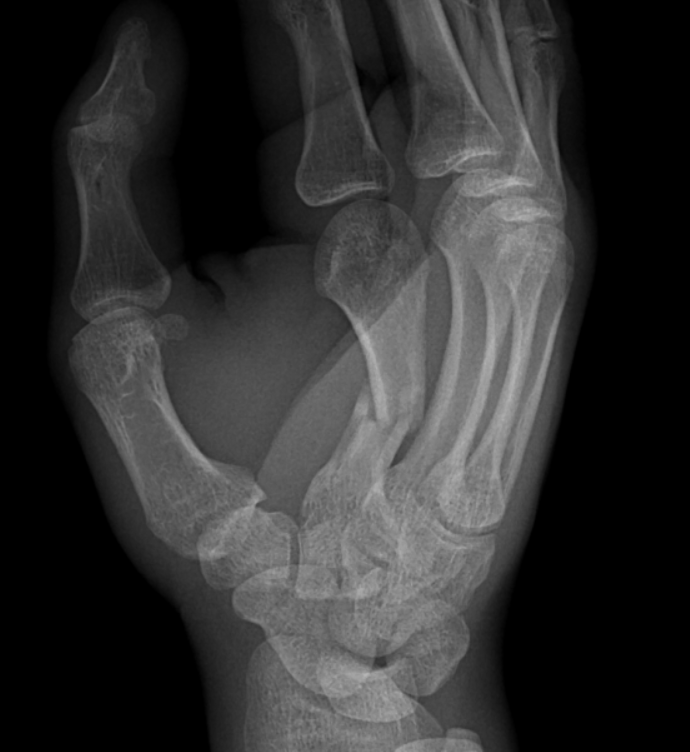

Клинический случай: остеосинтез перелома 2 пястной кости — до операции

Пациент с нестабильным переломом 2 пястной кости. Документируем боль, отёк и ограничения движений перед оперативным лечением.